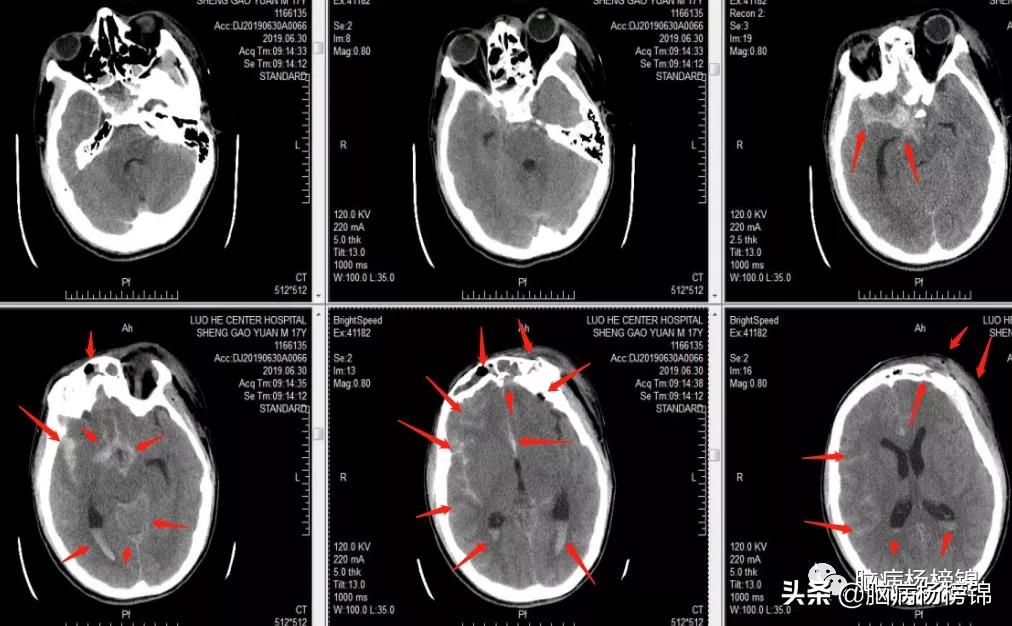

2小时余前患者车祸摔伤,头部着地,伤后出现意识不清,伴头面部出血,左侧额部、左侧上下眼睑、左侧嘴唇有裂伤,无呕吐、呼吸困难、大小便失常等不适,急打120来我院,以“开放性颅脑损伤重型”为诊断收入ICU。

颅骨多发骨折,积气。

蛛网膜下腔、脑室内、硬膜外,都是血液。

急诊头颅CT:左侧额叶脑挫裂伤;蛛网膜下腔出血;双侧额部硬膜下血肿;额骨、左侧鼻骨、双侧筛窦壁、左侧眼眶上壁及外侧壁、右侧眼眶上壁及左侧颧骨多发骨折;颅内积气;额部及颌面部软组织肿胀、积气;双侧额窦、筛窦、蝶窦及左侧上颌窦积液;胸部CT:双肺渗出性病变。